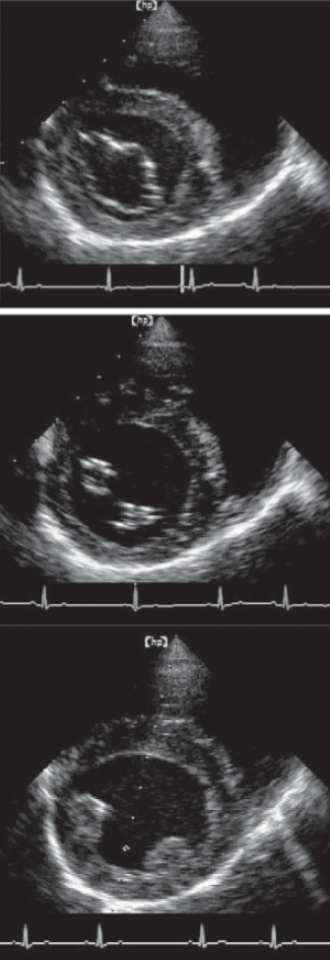

Name the ECHO VIEW and STRUCTURES

RPS LONG AXIS

LPS SHORT AXIS